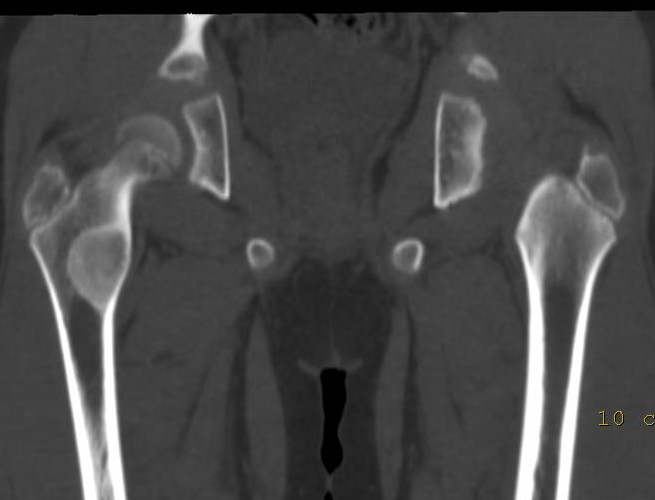

以下是引用lkc8963在2009-2-23 9:48:00的发言:[br]骨纤维性病变--非骨化性纤维瘤或局灶性骨纤首先考虑.理由:磨玻璃改变,边界清,向髓腔侧及皮质侧膨胀.最需鉴别内生软骨瘤,请楼主在轴扫上看有无点环状钙化,本例第二张图片上似见钙化,如有钙化首先考虑软骨源肿瘤.

以下是引用zbp537在2009-2-23 9:49:00的发言:[br]典型的磨玻璃样改变,考虑骨纤或骨化性纤维瘤。